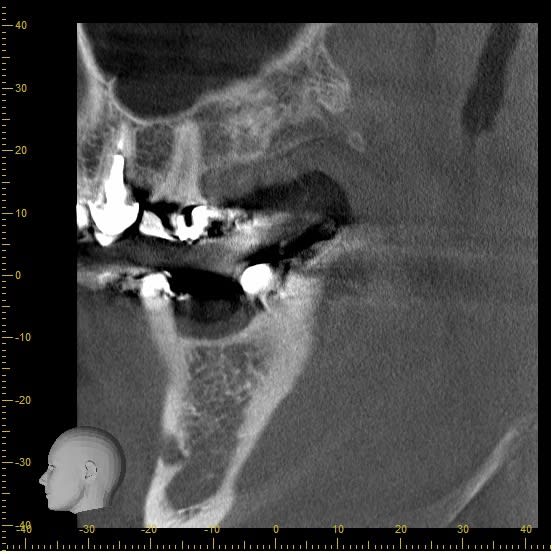

Voici une planification via I dixel apres le cone beam en vue implantation de 46.

Voici les différentes coupes et la simulation d'un implant 4,3 x 11,5 (nobel replace CC)

Que pensez vous de mon choix d'implant ?

Que pensez vous de la densité osseuse ?

Des remarques particulières par rapport à ce scanner ?